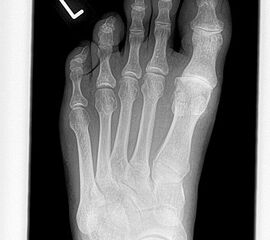

• Röntgenaufnahmen des Vorfußes (unter Belastung) im dorsoplantaren und seitlichen Strahlengang (Abb. 1a+b)

• Beurteilung des Erkankungsstadiums anhand der typischen Arthrosekriterien (Einteilung nach Regnauld) 2

• Beurteilung des Intermetatarsal-Winkels (IMA), des Hallux valgus-Winkels (HVA), mögliche Korrektur der des IMA von 6° durch alleinige Arthrodese, darüber hinaus evtl. zusätzliche MT-I-Korrektur notwendig 101112

• Beurteilung des Metatarsale-Index und der Zehenlänge DI und II, insbesondere nach Voroperationen hinsichtlich einer evtl. notwendigen Verlängerung des ersten Strahls durch Knochenspaninterposition